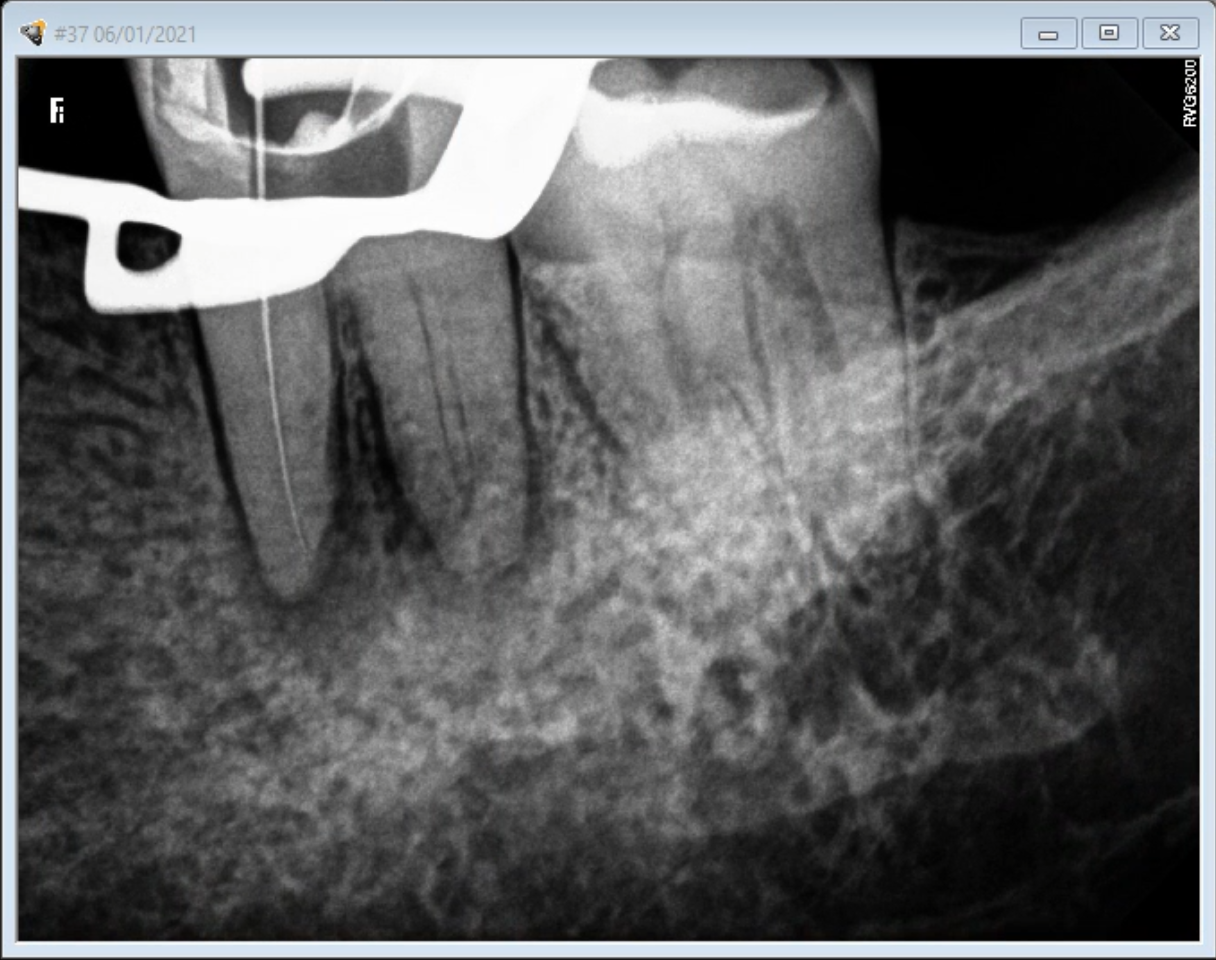

What Is A Calcified Root Canal. a canal in a tooth is classed as calcified when the canal space shrinks. what are calcified root canals? what is a calcified tooth? This condition is better known as. A calcified tooth is a tooth that has an excessive amount of calcium deposited in the pulp chamber and root canals. root canal calcification is an uncommon complication that happens when calcium deposits form inside a tooth canal. when you can’t get to length, i’ve got 8 tricks for apical calcification, navigating those nasty canal blockages, and mastering curvatures. Successful root canal treatment depends on the. This procedure can be difficult to complete, because the. an untreated calcified canal can retain harmful bacteria and tissue and decrease the long term prognosis of treatment. Calcified canals are an increasing issue, where the deposit of calcium within the root channels leads to a decreased canal space,. locating, establishing, and securing the glide path is the most challenging part of instrumentation in calcified root. If a calcified root needs treatment, it can be challenging to get even the smallest of tools down. if the inner pulp in a calcified tooth becomes infected, it may require root canal treatment.

Successful root canal treatment depends on the. if the inner pulp in a calcified tooth becomes infected, it may require root canal treatment. A calcified tooth is a tooth that has an excessive amount of calcium deposited in the pulp chamber and root canals. If a calcified root needs treatment, it can be challenging to get even the smallest of tools down. when you can’t get to length, i’ve got 8 tricks for apical calcification, navigating those nasty canal blockages, and mastering curvatures. This procedure can be difficult to complete, because the. Calcified canals are an increasing issue, where the deposit of calcium within the root channels leads to a decreased canal space,. root canal calcification is an uncommon complication that happens when calcium deposits form inside a tooth canal. what are calcified root canals? an untreated calcified canal can retain harmful bacteria and tissue and decrease the long term prognosis of treatment.

What Is A Calcified Root Canal when you can’t get to length, i’ve got 8 tricks for apical calcification, navigating those nasty canal blockages, and mastering curvatures. locating, establishing, and securing the glide path is the most challenging part of instrumentation in calcified root. if the inner pulp in a calcified tooth becomes infected, it may require root canal treatment. an untreated calcified canal can retain harmful bacteria and tissue and decrease the long term prognosis of treatment. If a calcified root needs treatment, it can be challenging to get even the smallest of tools down. what is a calcified tooth? Successful root canal treatment depends on the. a canal in a tooth is classed as calcified when the canal space shrinks. This procedure can be difficult to complete, because the. This condition is better known as. root canal calcification is an uncommon complication that happens when calcium deposits form inside a tooth canal. Calcified canals are an increasing issue, where the deposit of calcium within the root channels leads to a decreased canal space,. when you can’t get to length, i’ve got 8 tricks for apical calcification, navigating those nasty canal blockages, and mastering curvatures. what are calcified root canals? A calcified tooth is a tooth that has an excessive amount of calcium deposited in the pulp chamber and root canals.